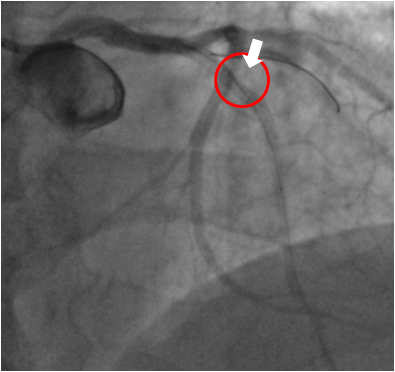

冠動脈疾患の可能性が高いと判定された場合は心臓カテーテル検査にて確定診断を行います。カテーテルと呼ばれる直径2mm程度の細い管を足の付け根や手首の動脈から挿入し、心臓の出口付近の冠動脈に引っ掛けて造影剤を注入、撮影を行い冠動脈の狭窄や閉塞の度合いを調べます。当院では殆どの症例において負担の少ない手首の血管から検査と治療を第一選択部位として行っており、治療を行った場合でも合併症がなくスムーズに終了した場合は通常1泊もしくは2泊で退院可能となります。

心臓カテーテル検査(冠動脈造影)にて狭窄や閉塞を確認した血管に対しては、バルーンやステントを用いて血管を広げて血流を確保します。

心臓カテーテル 治療前 心臓カテーテル 治療後